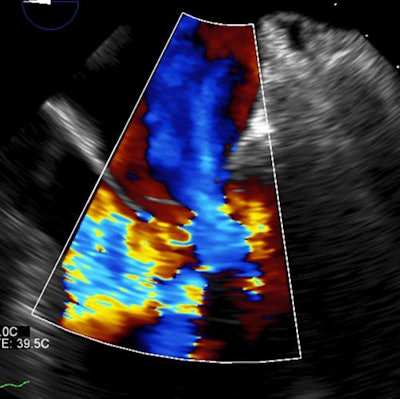

In this case of atypical pulmonary edema, predominant left-sided edema is due to acute mitral valve rupture with eccentric regurgitation seen at echocardiography. Bilateral pleural effusion is also seen. All images courtesy of Dr. Juan Arenas-Jiménez, PhD.